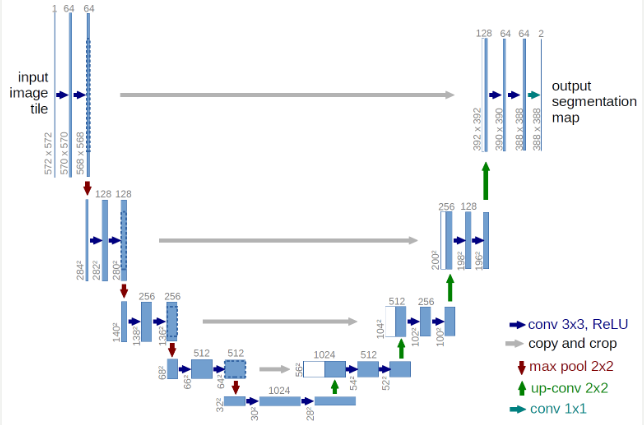

このU-Netのモデル概要は、以下のサイトを参考にしてください。

U-Net: Convolutional Networks for Biomedical Image Segmentation

バイオメディカルのセグメンテーションのためのモデルのようです。